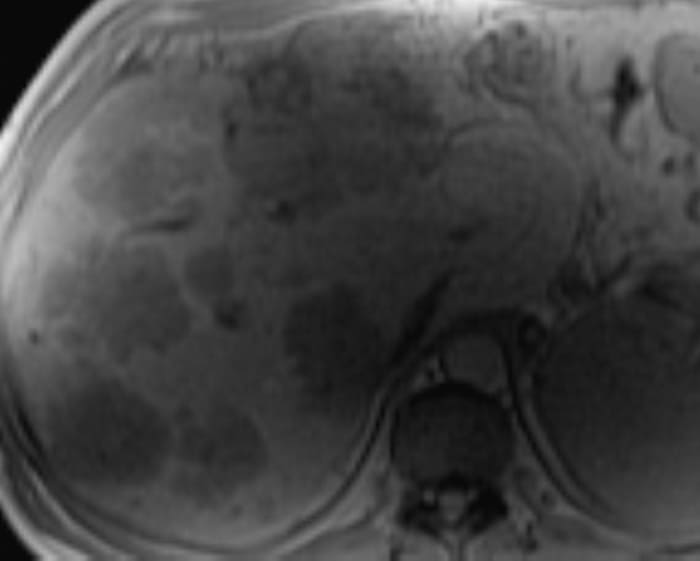

Di căn gan

» Thông tin: Nam giới – 37 tuổi.

» Lâm sàng: Tiền sử K đại tràng.